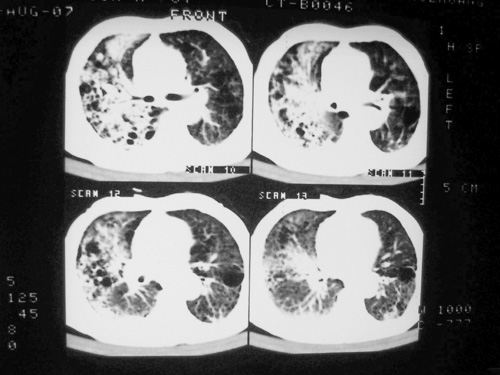

老年男性,70岁。煤矿工人20年。一周前咳嗽、发烧,拍x片考虑矽肺可能。始终咳嗽行ct检查,发现弥漫性病变,似感染但密度很高,细支气管肺泡癌无法排除,请老师给予指点。

一般矽肺多为双肺融合状,团块状高密度结节影.并散在多处小结节影.可这个病人只表现在单肺,并没有融合结节影.一周前的x片没显示大片高密度影,可定位扫描时(图象忽略传了),右肺已经清晰显示大片高密度影.作比较感觉是新病灶.可实际表现又不象,所以才拿来让各位老师看看.